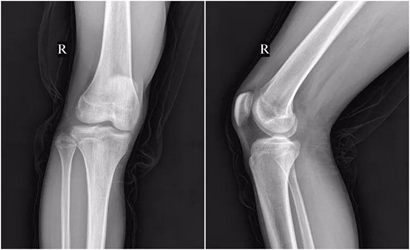

适应症:适用于骨折、脱位、关节间隙的改变、骨性结构的初步评估等。

优势:成本低,辐射剂量相对较低,检查速度快。

局限性:对软组织的显像能力较差,不能清晰显示肌肉、韧带、软骨等结构。